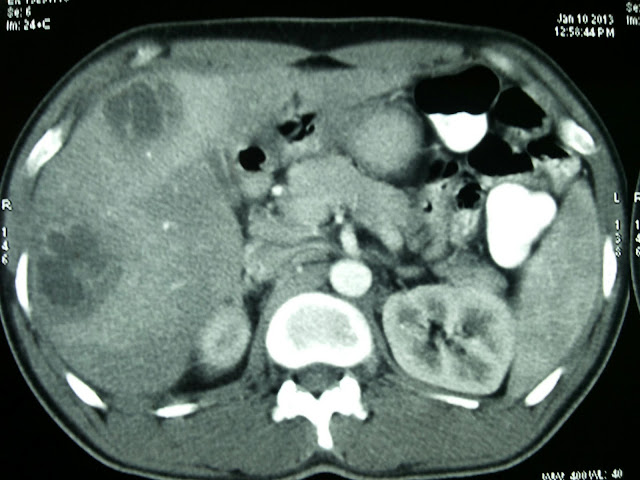

Ct scan pyogenic liver abscess